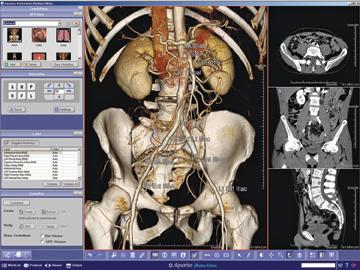

Several features/plug-ins have been added to aycan’s OsiriX PRO workstation to significantly expand its functionality. The new features will be showcased at Radiological Society of North America (RSNA) 2012, including the new aycan mobile iPad app, advanced hanging protocols, vessel analysis, 4-D ROI statistics and ejection fraction.

Aycan Medical Systems will highlight its latest vendor-neutral archiving, viewing, printing, and integration solutions and services designed to improve workflow efficiency and drive down costs, at this year’s RSNA, including aycan mobile iPad app.

aycan Medical Systems will highlight its latest vendor-neutral archiving, viewing, printing, and integration solutions and services designed to improve workflow efficiency and drive down costs, at this year’s RSNA, including aycan store (PACS).